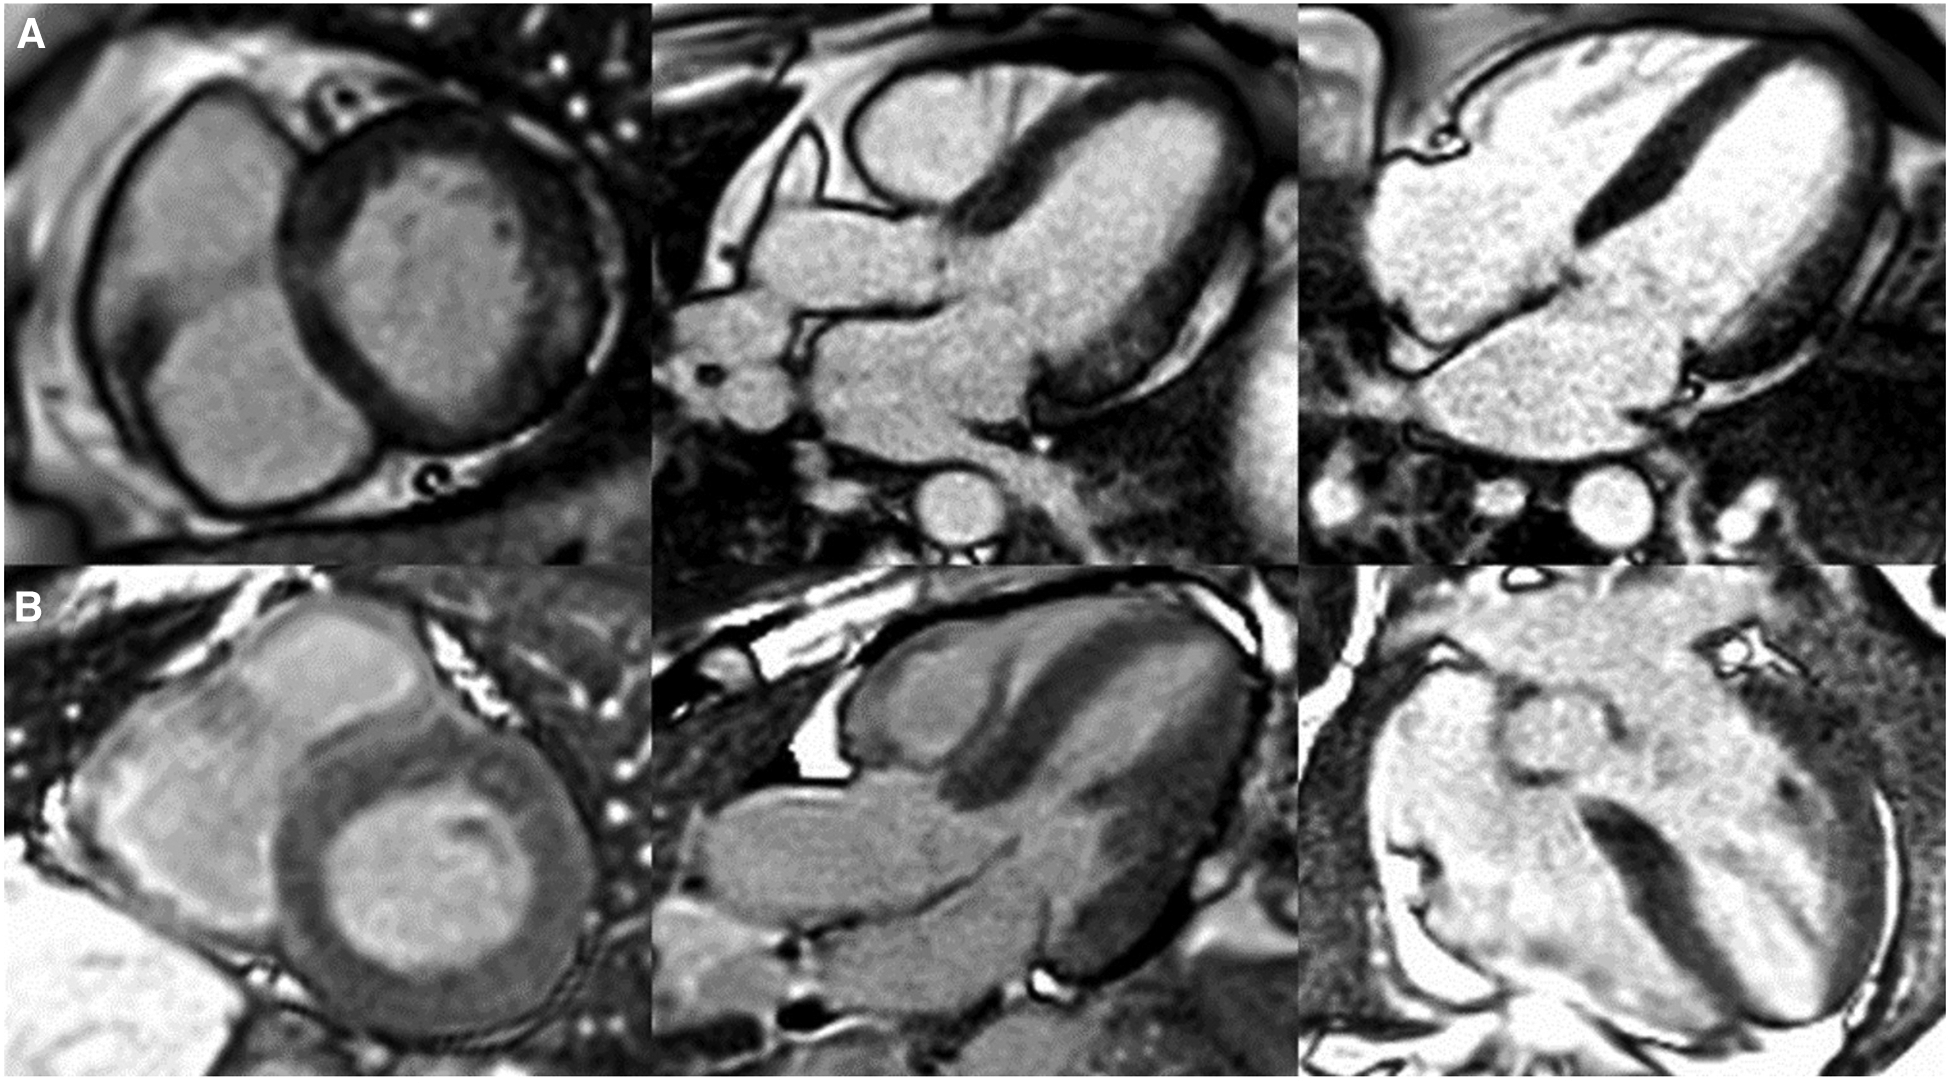

Patterns of cardiac late gadolinium enhancement (LGE) via MRI in Fabry disease. Caption: cardiovascular magnetic resonance LGE images captured using phase sensitive inversion recovery sequences with motion correction. Panel (A), left to right: basal short axis, 3 chamber and 4 chamber views depicting pathognomonic basal inferolateral wall fibrosis in a female patient (60 years old) with no left ventricular hypertrophy (maximal wall thickness = 7 mm). Panel (B), left to right: basal short axis, 3 chamber and 4 chamber views depicting lack of LGE, therefore fibrosis in a male Fabry patient (51 years old) with left ventricular hypertrophy (maximal wall thickness = 17 mm in the basal antero-septum).

For instance, in females, fibrosis manifests as late gadolinium enhancement (LGE) via cardiac magnetic resonance imaging prior to the development of left ventricular hypertrophy, whereas in males, left ventricular hypertrophy typically precedes fibrosis (44), see Figure 2. LGE is a valuable imaging technique to visualise fibrotic tissues due to their uptake of the gadolinium contrast agent, thereby enabling the identification of the extent and progression of fibrosis. In Fabry disease, LGE serves as an essential tool in disease severity assessment, progression monitoring, and guiding treatment strategies.